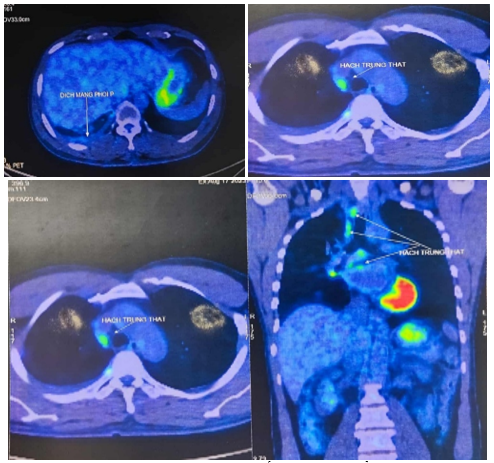

Bệnh nhân được chụp PET/CT tại Bệnh viện Vinmec cho kết quả: Các nốt đặc rải rác thùy giữa và dưới phổi phải, các nốt lớn tăng chuyển hoá FDG (suvmax 3,6), ít dịch màng phổi dày 9mm, nhiều nốt rải rác màng phổi thành ngực, hạch nhóm 2R,4R/7 rốn phổi phải, hạch lớn KT 17x10mm.

Hình 4: Hình ảnh chụp PET/CT: Hạch trung thất, dịch màng phổi phải (mũi tên chỉ)